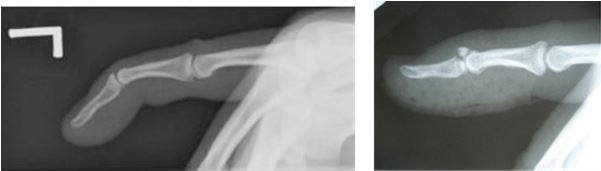

Diagnosis

X-ray to confirm if the mallet finger is a bony or tendon injury.